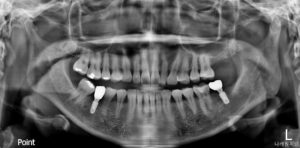

모든 치료가 마무리된

파노라마 사진인데요.

환자분께서는 어금니 하나 정도

상실한 것 정도야 하고 방치하시다가

이번 치료를 통해

양측 저작이

훨씬 편안해지신 것을 확인하시고는

치아의 소중함을 몸소 느끼셨다며

앞으로 관리를 더 잘해주시겠다고

약속해 주셨습니다.